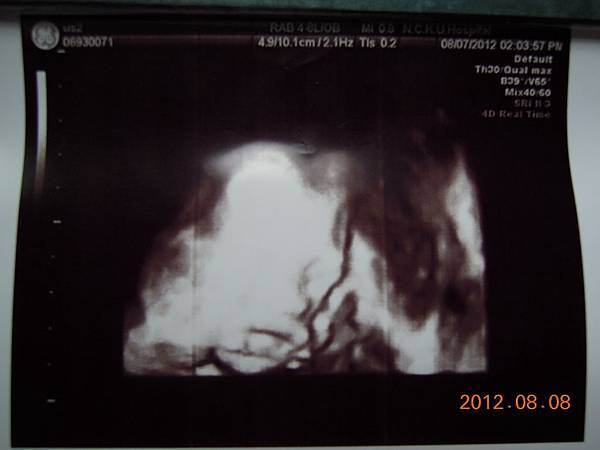

後來還有問他關於四D超音波的問題,沒想到女醫師說,那沒什摩啊~等依下我幫你照個合成給你看,這種只要有儀器都可以照,沒什麼技術可言~